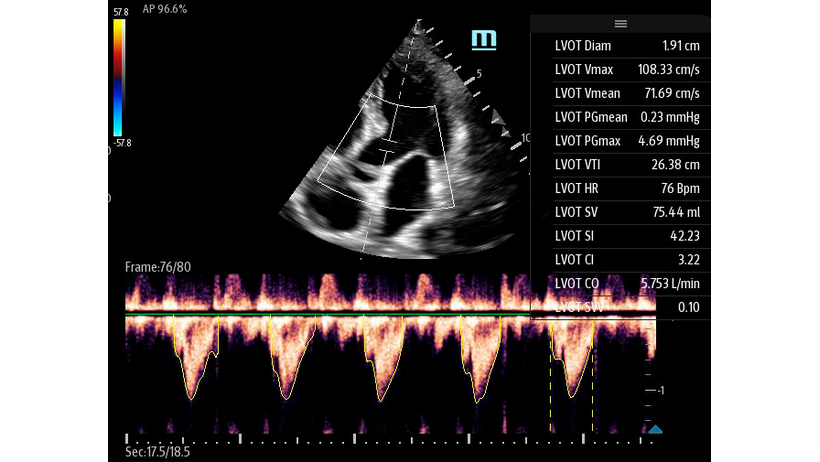

Автоматическая оценка потока выносящего тракта – Smart VTI

Чтобы использовать уравнение, нужно получить поток выносящего тракта левого желудочка в PW допплере — это достаточно кропотливая работа. В ультразвуковых системах Mindray Resona i9 эта задача решается автоматической оценкой потока выносящего тракта – Smart VTI.

Доктору остается получить 5-ти камерное сечение сердца и нажать одну кнопку на сенсорном экране. Прибор сам выберет расположение контрольного объема, получит спектрограмму и обведет спектр с расчётом всех показателей. Быстро и эффективно.